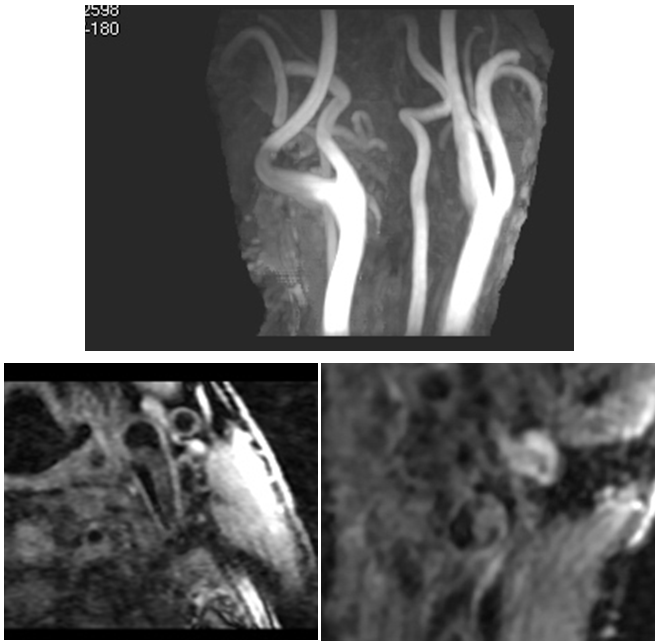

高分辨MR扫描所示图中患者左颈内动脉起始段走形迂曲,左侧壁见条状偏心斑块,斑块表面不规整,内未见出血信号,增强扫描斑块不均匀强化。提示为易损斑块,建议临床进一步对症治疗